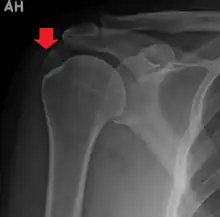

An x-ray showing calcific deposits in the area of the tendons of the rotator cuff muscles

Calcific tendinitis is typically diagnosed by physical examination and X-ray imaging.[1] During the formative phase, X-ray images typically reveal calcium deposits with uniform density and a clear margin.[1] In the more painful resorptive phase, deposits instead appear cloudy and with unclear margins.[1] By arthroscopy, formative stage deposits appear crystalline and chalk-like, while resorptive stage deposits appear smooth resembling toothpaste.[1] Ultrasound is also used to locate and assess calcium deposits. In the formative stage, deposits are hyperechoic and arc-shaped; in the resorptive stage deposits are less echogenic and appear fragmented.[1][3]